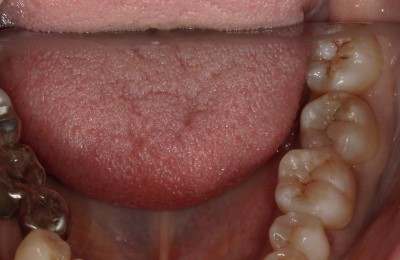

CASE03ダイレクトボンディング

Before

After

| 主訴 | できるだけ歯を削らずに銀歯を白くしたい。 |

|---|---|

| 治療方法 | 銀歯を除去した後、ダイレクトボンディング法によりコンポジットレジンを用いて修復した。 |

| 治療期間 | 1回 |

| リスク | 長年使用することによる着色。咬合圧が強い場合破折することがある。 |

| 費用 | 55,000円×2(税込み) |